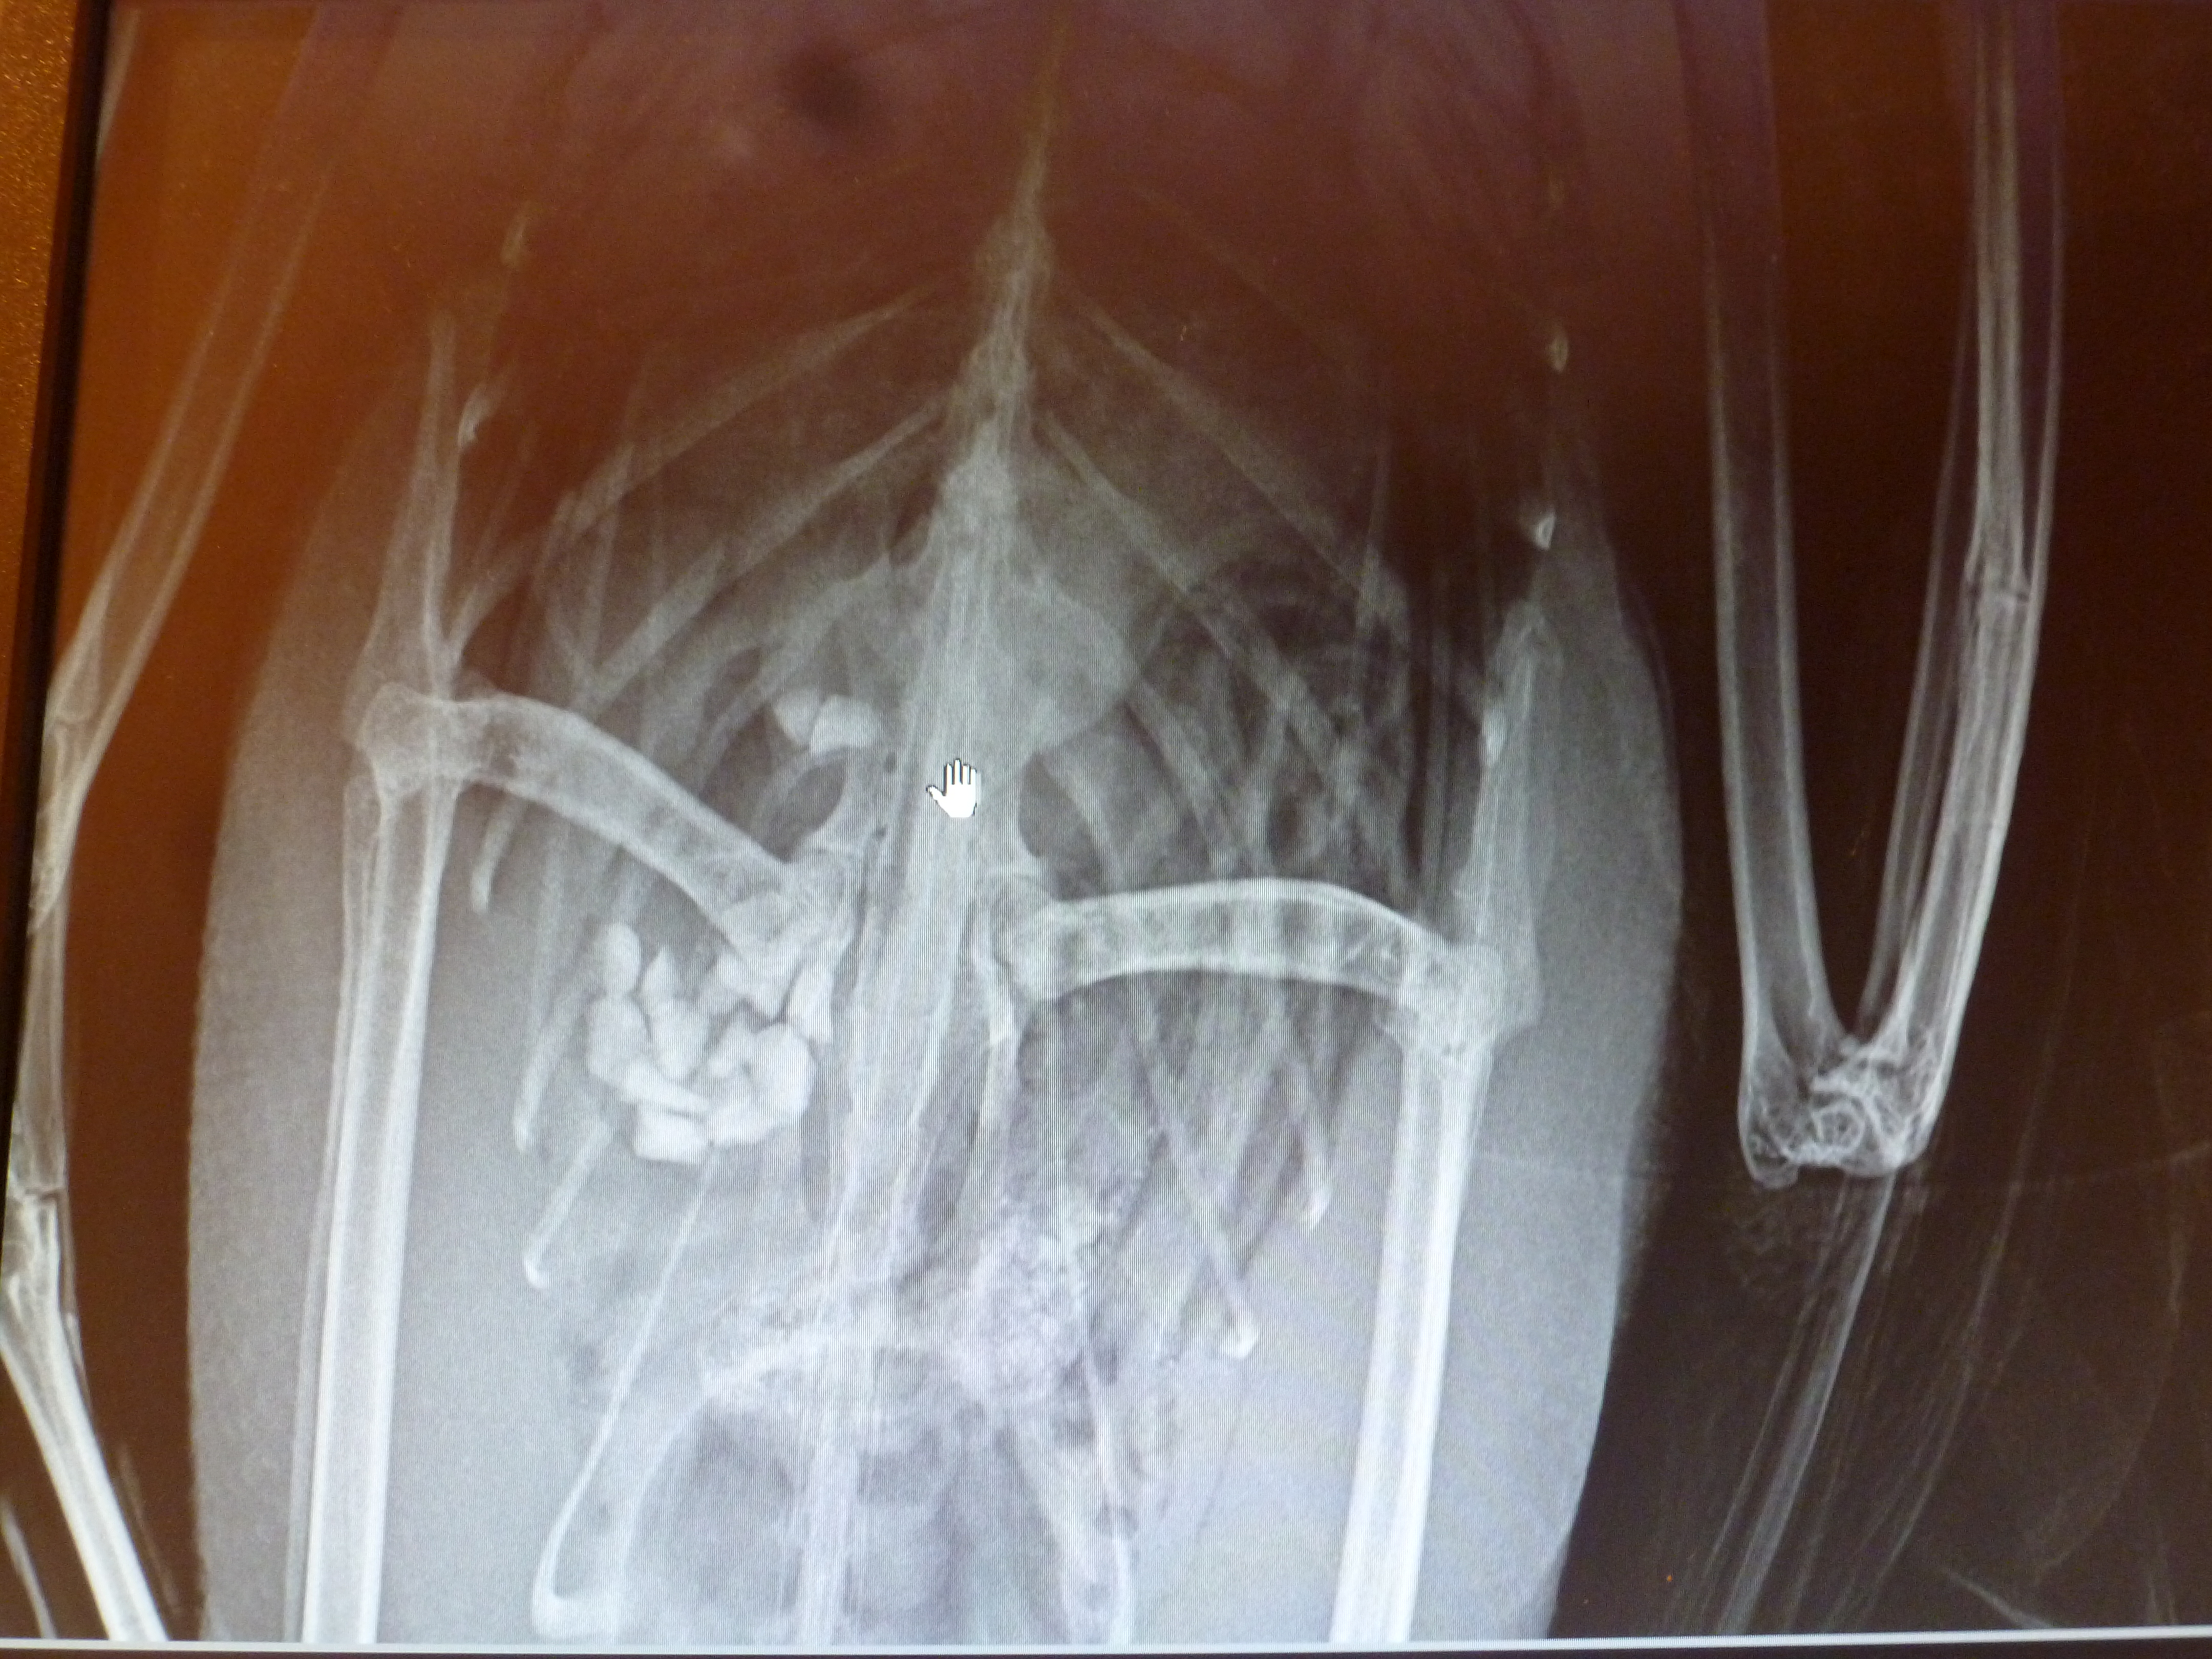

Initial x-rays revealed not just one hook, but two hooks similar to a rig for walleye fishing. One of the hooks had already made its way deep into the proventriculus. The proventriculus is one part of two parts of a bird’s stomach. It has very acidic pH which softens food to make it easier for the bird to digest. There was also a spot on the x-ray which could’ve been a lead sinker or a rock. If it was indeed a lead sinker, the possibility of lead poisoning was highly likely.